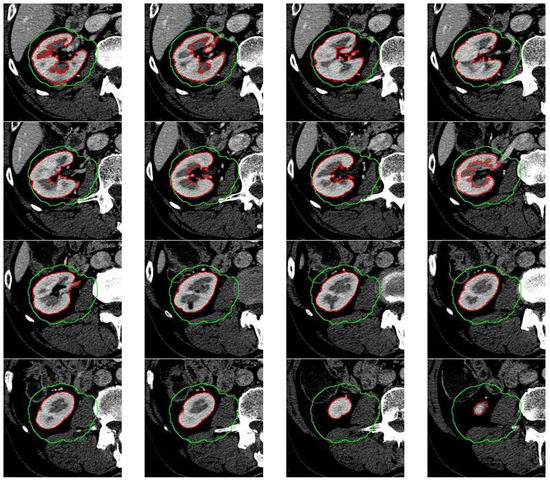

In Figure 8 and Figure 9 a visualization of selected slices for two cases is presented. The results were obtained after using a complete system with U-Net support. Green is the starting search area while red is the automatic kidney system.

The analysis of both cases shows that the system is characterized by high accuracy of diagnosis both for each part of the abdominal section.

Figure 8. The image shows a visualization of selected slices. Green is the starting search area while red is the automatic kidney system.

Figure 9. The image shows a visualization of selected slices. Green is the starting search area while red is the automatic kidney system.